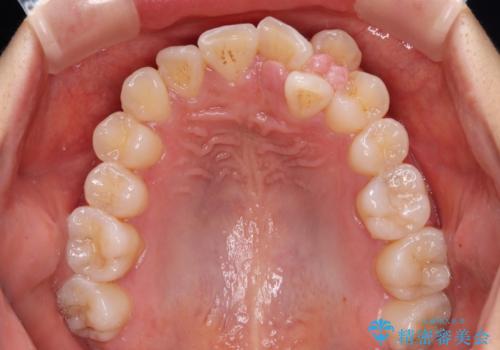

- 左上の前歯のがたつきを主訴に来院された患者様です。

上顎歯列が下顎の歯列に対して狭小であり、一部下顎の奥歯が上顎よりも外側に位置している状態でした。

上顎の歯列を拡大しスペースを設け、さらに左上の小臼歯を一本抜歯し左上の八重歯を歯列内に入れ整えていくことにしました。